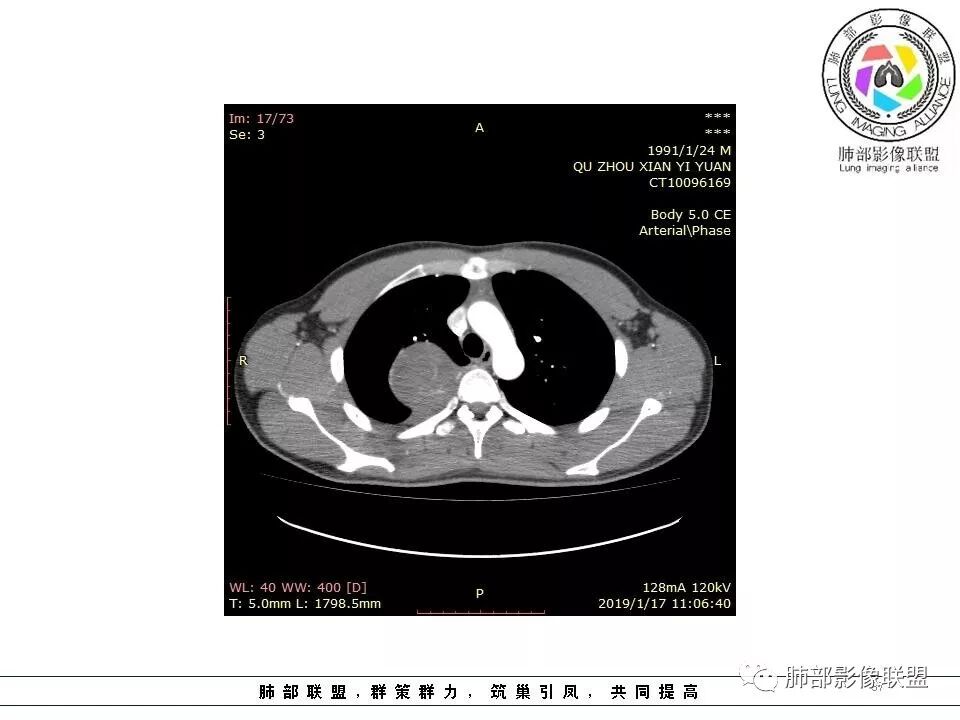

右后纵膈脊柱旁软组织占位,形态规则类圆,边缘光整,肺组织受压,胸膜尾,肋间动脉供血。中度不均匀延迟强化。

右后纵膈脊柱旁软组织占位,边界清晰,光整,肺组织受压。胸膜被掀起,肋间动脉供血,中度不均匀延迟强化。考虑神经鞘瘤,不除外纤维瘤

右后纵膈脊柱旁软组织影,与纵隔结构分界不清,形态规则类圆,边缘光整,肺组织受压,胸膜尾,肋间动脉供血。肺动脉推移,中度不均匀延迟强化。考虑神经来源,神经鞘瘤,神经纤维瘤二者不易鉴别。

青年男性,间断胸痛;右侧脊柱旁可见一类圆形软组织密度影,密度欠均匀,增强扫描呈轻中度持续强化,邻近肺组织及肺动脉推移,可见肋间动脉供血,部分胸膜下脂肪可见,部分层面似见与右侧椎间孔相连。考虑后纵隔神经源性肿瘤。

1.右上胸内脊柱旁类圆形肿块,质地似乎比较坚实,密度稍显不均,但未显示明确的坏死。

2.肋间动脉病供血也提示肿块来自后纵隔?